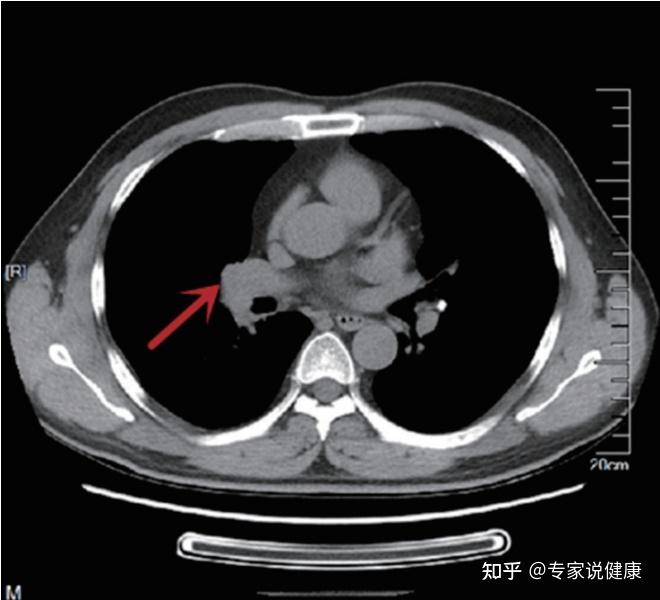

胸部ct平扫示左下肺占位肺癌

图片尺寸1080x1121